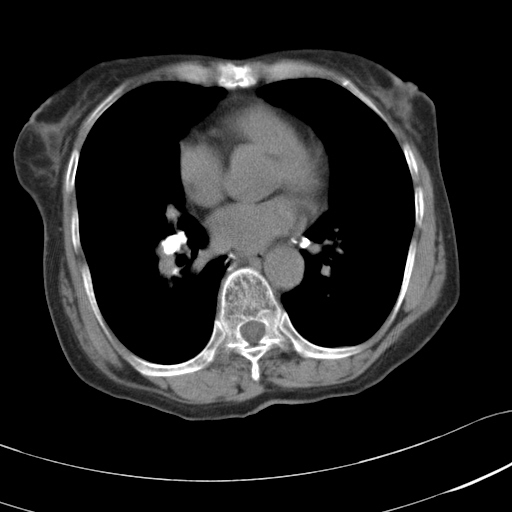

以下是引用hhcckk在2007-3-2 14:51:00的发言:[br]考虑结核球可能性大,依据[br]1病灶在下叶背段,结核的好发部位[br]2病灶内有大量的钙化,纵隔内有大量的淋巴结钙化[br]3重要的是半年前与现在相比无变化,假如是肿瘤的话不会这么‘善良’[br]4病灶周围卫星灶不明显,病灶有毛刺,胸膜凹陷,肿瘤不能完全排除,有条件的话最好做个活检

以下是引用liuyue在2007-3-2 17:15:00的发言:[br]1位置:右上叶后段[br]2性质:大分叶、粗长毛刺、条状斑片状钙化、纵隔多发淋巴结钙化,无强化,故考虑:肺结核灶(陈旧)